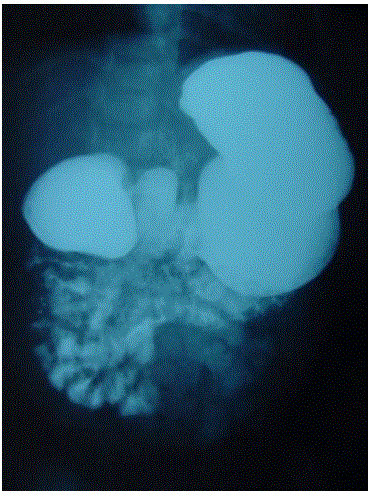

Lactente de 10 meses portador de Síndrome de Down é encaminhado ao cirurgião pediátrico para realização de fundoplicatura por refluxo grave com dificuldade de ganho ponderal. A mãe relata que o filho apresenta vômitos alimentares 2 a 3 vezes ao dia e o quadro se intensificou aos 6 meses, quando foram introduzidos alimentos pastosos. Traz um exame contrastado que revela a imagem a seguir:

Qual é a melhor conduta?